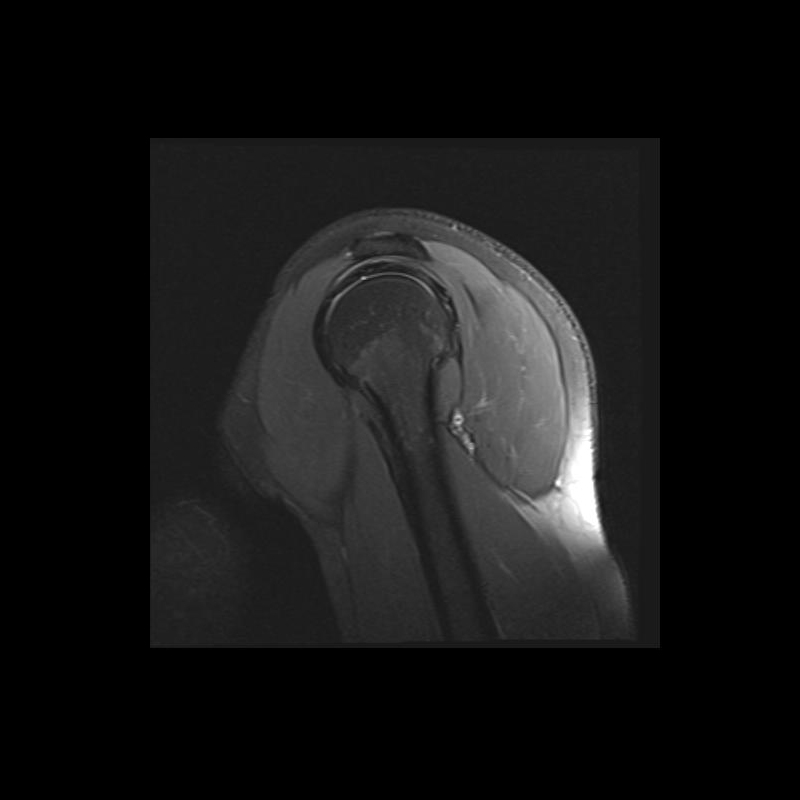

Shoulder MRI Anatomy